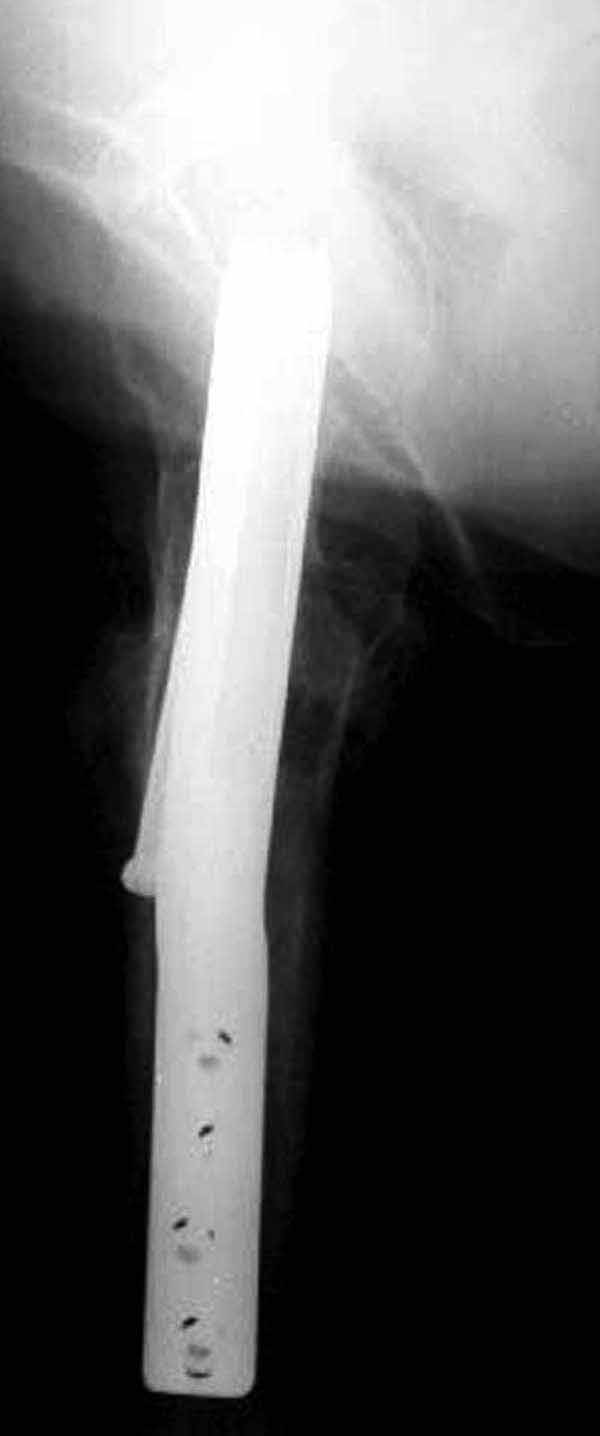

У больных с ожирением и соматическими заболеваниями нежелательно открывать место перелома. Гвозди от DePuy с двумя шурупами рассчитаны для переломов бедра, и приходилось их применить для фиксации подвертельных переломов, но более адекватную фиксацию создает Gamma 3.

Здесь подобный случай, где стрессовый перелом обнаружен через 2 недели после фиксации. Применен Blade Plate с дополнительными шурупами.